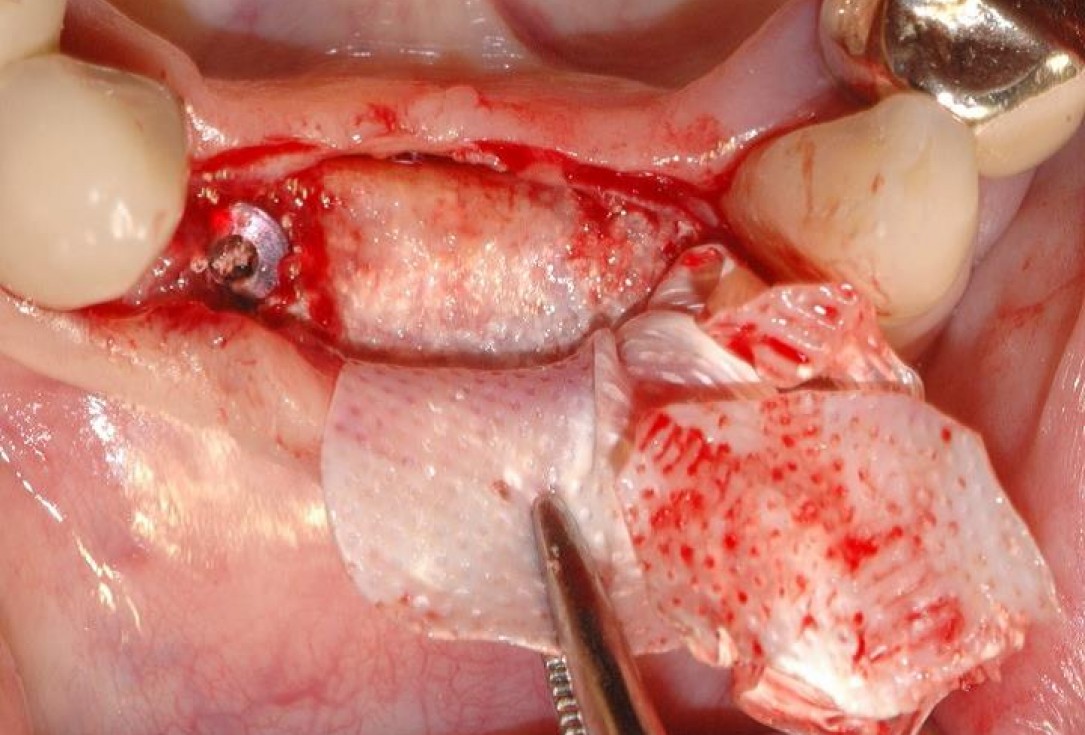

5/15 - Ridge augmentation with maxresorb® and covering with a fixed non-resorbable membraneSoft tissue augmentation and GBR with mucoderm® and maxresorb® - Dr. S. Scherg

6/15 - Soft tissue augmentation with mucoderm® and fixation with the flapSoft tissue augmentation and GBR with mucoderm® and maxresorb® - Dr. S. Scherg